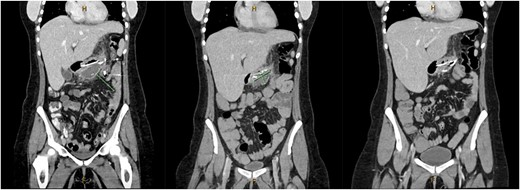

A 31-year-old female, 6 weeks post laparoscopic sleeve gastrectomy presented to the emergency department with epigastric pain and vomiting. Initial bloods showed raised inflammatory markers with a white cell count of 15.5 × 109/L and C-reactive protein of 342 mg/L. Initial CT on presentation showed the presence of a 14 × 7 × 5 cm3 gas and fluid filled collection adjacent to the staple line (Fig. 1). The patient was resuscitated with adequate fluids and kept nil by mouth. Prompt broad spectrum antibiotics were commenced. An 8Fr firm nasobiliary tube was placed directly into the collection via the defect near the GOJ under endoscopic guidance and placed on suction. During the same endoscopic procedure, a feeding nasojejunal tube was placed to ensure adequate nutrition. Given the extent of the collection, sequential advancement of the nasobiliary tube over the course of 23 days was required to ensure adequate drainage. The collection was monitored with repeat CT scans until resolution (Fig. 2). The GOJ defect was then endoscopically closed with an over the scope clip on Day 23 post presentation. The patient was discharged home post a repeat CT showing complete resolution of the collection and no oral contrast medium extending into the site of the previous collection.

Coronal CT images on Days 2, 9 and 14 post insertion of nasobiliary drainage tube to sleeve gastrectomy staple line collection showing interval reduction in collection size.